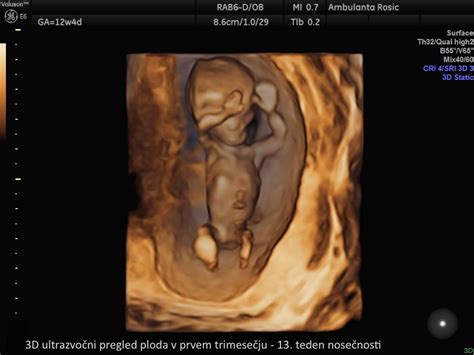

Prvo trimesesečje (do 13. tedna)

To je obdobje hitrega razvoja, kjer se zarodek razvije v fetus. Že do konca prvega trimesesečja imajo vsi vitalni organi svoje mesto in začno delovati.

- Rast in razvoj organov: Do 9. tedna plod že doseže dolžino 14-20 mm in težo 1 g. Srčni utrip je povišan, krvni pritisk pa pogosto znižan. V 10. tednu plod meri 3.1 cm in tehta 4 g. Ledvice, jetra in pljuča že funkcionirajo, čeprav se bodo še celotno nosečnost razvijali in dozorevali. V 11. tednu plod meri 4.1 cm in tehta 7 g, njegova teža in dolžina pa se bosta do 20. tedna povečali za 30-krat oziroma 3-krat. V pljuča plod že vdihava majhne količine plodovnice, kar je ključno za njihov razvoj, ušesa pa se postavijo na svoje mesto. Začnejo se tudi kratki ciklusi spanja. V tem obdobju lahko nosečnica pridobi 500-1000 g na mesec. Do 13. tedna plod meri 7.4 cm in tehta do 23 g, glavica pa še vedno predstavlja polovico njegove dolžine. Jutranje slabosti običajno pojenjajo, pojavi se lahko zgaga.